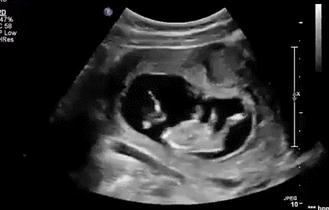

等到他再大点的时候,“蛙泳”项目已经无法进行了,但是你以为他长大点了就会听话、懂事,当个乖宝宝吗?

咦?这地儿怎么越来越小了,不管,我挤,我顶......

顶了这么久,“房子”怎么还是这么小?

管他呢,我要出去,我要潜水,我继续蹬腿,我蹬……